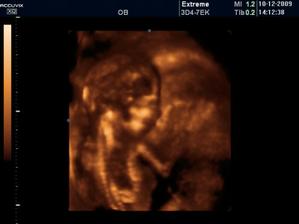

06/10/ bije srdííčko !!!!

Zaplatila jsem si ale přesto UTZ a vypada to,že budeme mit chlapečka 🙂) pry tak na 80% jistota je vždy až po porodu 🙂)

CHLAPEČEK POTVRZENY Dr Břeštákem ))